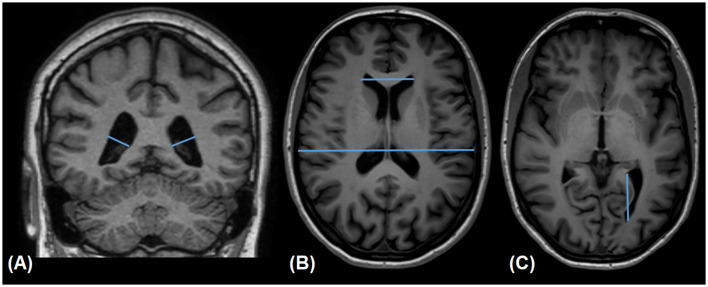

Methods: We conducted a retrospective analysis of magnetic resonance imaging (MRI) scans from 217 adult participants across 15 age groups, utilizing a stratified random sampling from a radiology database. MRI scans were analyzed for ventricular dimensions, and horn types (open, constricted, and closed). Statistical significance was defined as p-value < 0.05.

Results: Variants of the posterior horn were observed frequently, with open posterior horn being the most common in the left lateral ventricle (41%) and constricted type being the most common in the right lateral ventricle (37%). A significant correlation existed between the right and left horn types, but in most cases, there was a difference in type between the right and the left horns in the same individual. No significant association between age and the type of the posterior horns was found. However, there was a significant difference in the width and length of the horns between the open and other types, with open horns being wider and longer. Lastly, the left horn appeared longer than the right one.